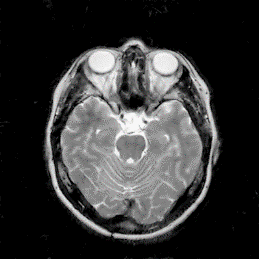

We provide numerous experiments to demonstrate the effectiveness of the proposed method in MR reconstruction, which compares with several iterative optimization-based and deep learning-based approaches. We employ three sampling masks: variable density sampling [2], cartesian sampling [39] and radial sampling [40], and a variety of sampling rates are set for each mask. An example of each mask is shown in Fig. 5. Then we consider the noisy settings and apply the proposed model into MR super-resolution. In addition, the ablation study on residual learnings is conducted to illustrate the effect of GRL and LRLs, and different initial learning rates are considered in experiments.

Figure 5: Three sampling masks with specfic sampling rates. (a) 20% variable density random sampling. (b) 25% cartesian sampling. (3) 30% radial sampling.